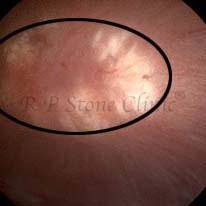

Kidney stone is a solid mass of CRYSTALS. It is the process of crystallization which initiates the formation of kidney stones. This happens in nephrons or units of kidney. Once a small crystal is formed, it can both grow & unite with other crystals leading to the formation of small concretion which eventually forms a stone. Once these large crystals detach from the collecting ducts, the process of stone formation starts in the renal collecting system. A recurrent kidney stone former is advised to know a little bit about something known as Randall’s plaque. Alexander Randall discovered plaques on the renal papillae eight decades back based on examination of 1154 pairs of autopsied Kidneys. He described these renal papillary lesions as cream colored or milk patch areas composed of calcium phosphate & calcium carbonate. These plaques could act as NIDUS for formation of KIDNEY STONE. Calcium Oxalate stone can form on this nidus & then detaches from this plaque to become a free floating stone in the collecting system of kidney

These images are taken as snap shots from the video recording of RIRS Surgery done at our hospital. These are Randall’s Plaques seen with Digital FLEX XC & Digital FLEX XC S. The cream or whitish patches are seen on the tips of RENAL PAPILLAE as seen in images below.